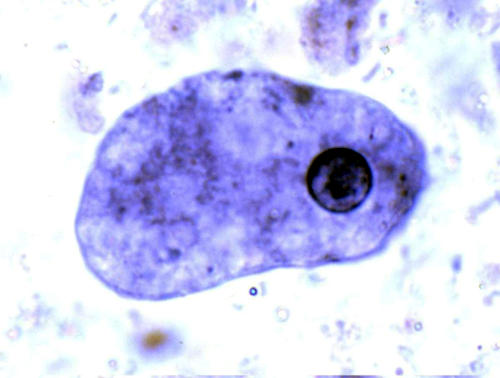

Дизентерийная амёба в анабиозе

Подвергаются анабиозу также амёбы, нематоды и другие черви, тихоходки, яйца и гусеницы насекомых, клетки и ткани амфибий и другие. Некоторые ткани (например, кровь) сохраняют способность переносить длительное и глубокое охлаждение без потери жизнеспособности при добавлении таких защитных веществ, как глюкоза, этиленгликоль, глицерин и других. Сперма животных после глубокого охлаждения жидким водородом сохраняет способность к оплодотворению.

У некоторых организмов анабиоз входит в нормальный цикл развития (семена, споры, цисты).